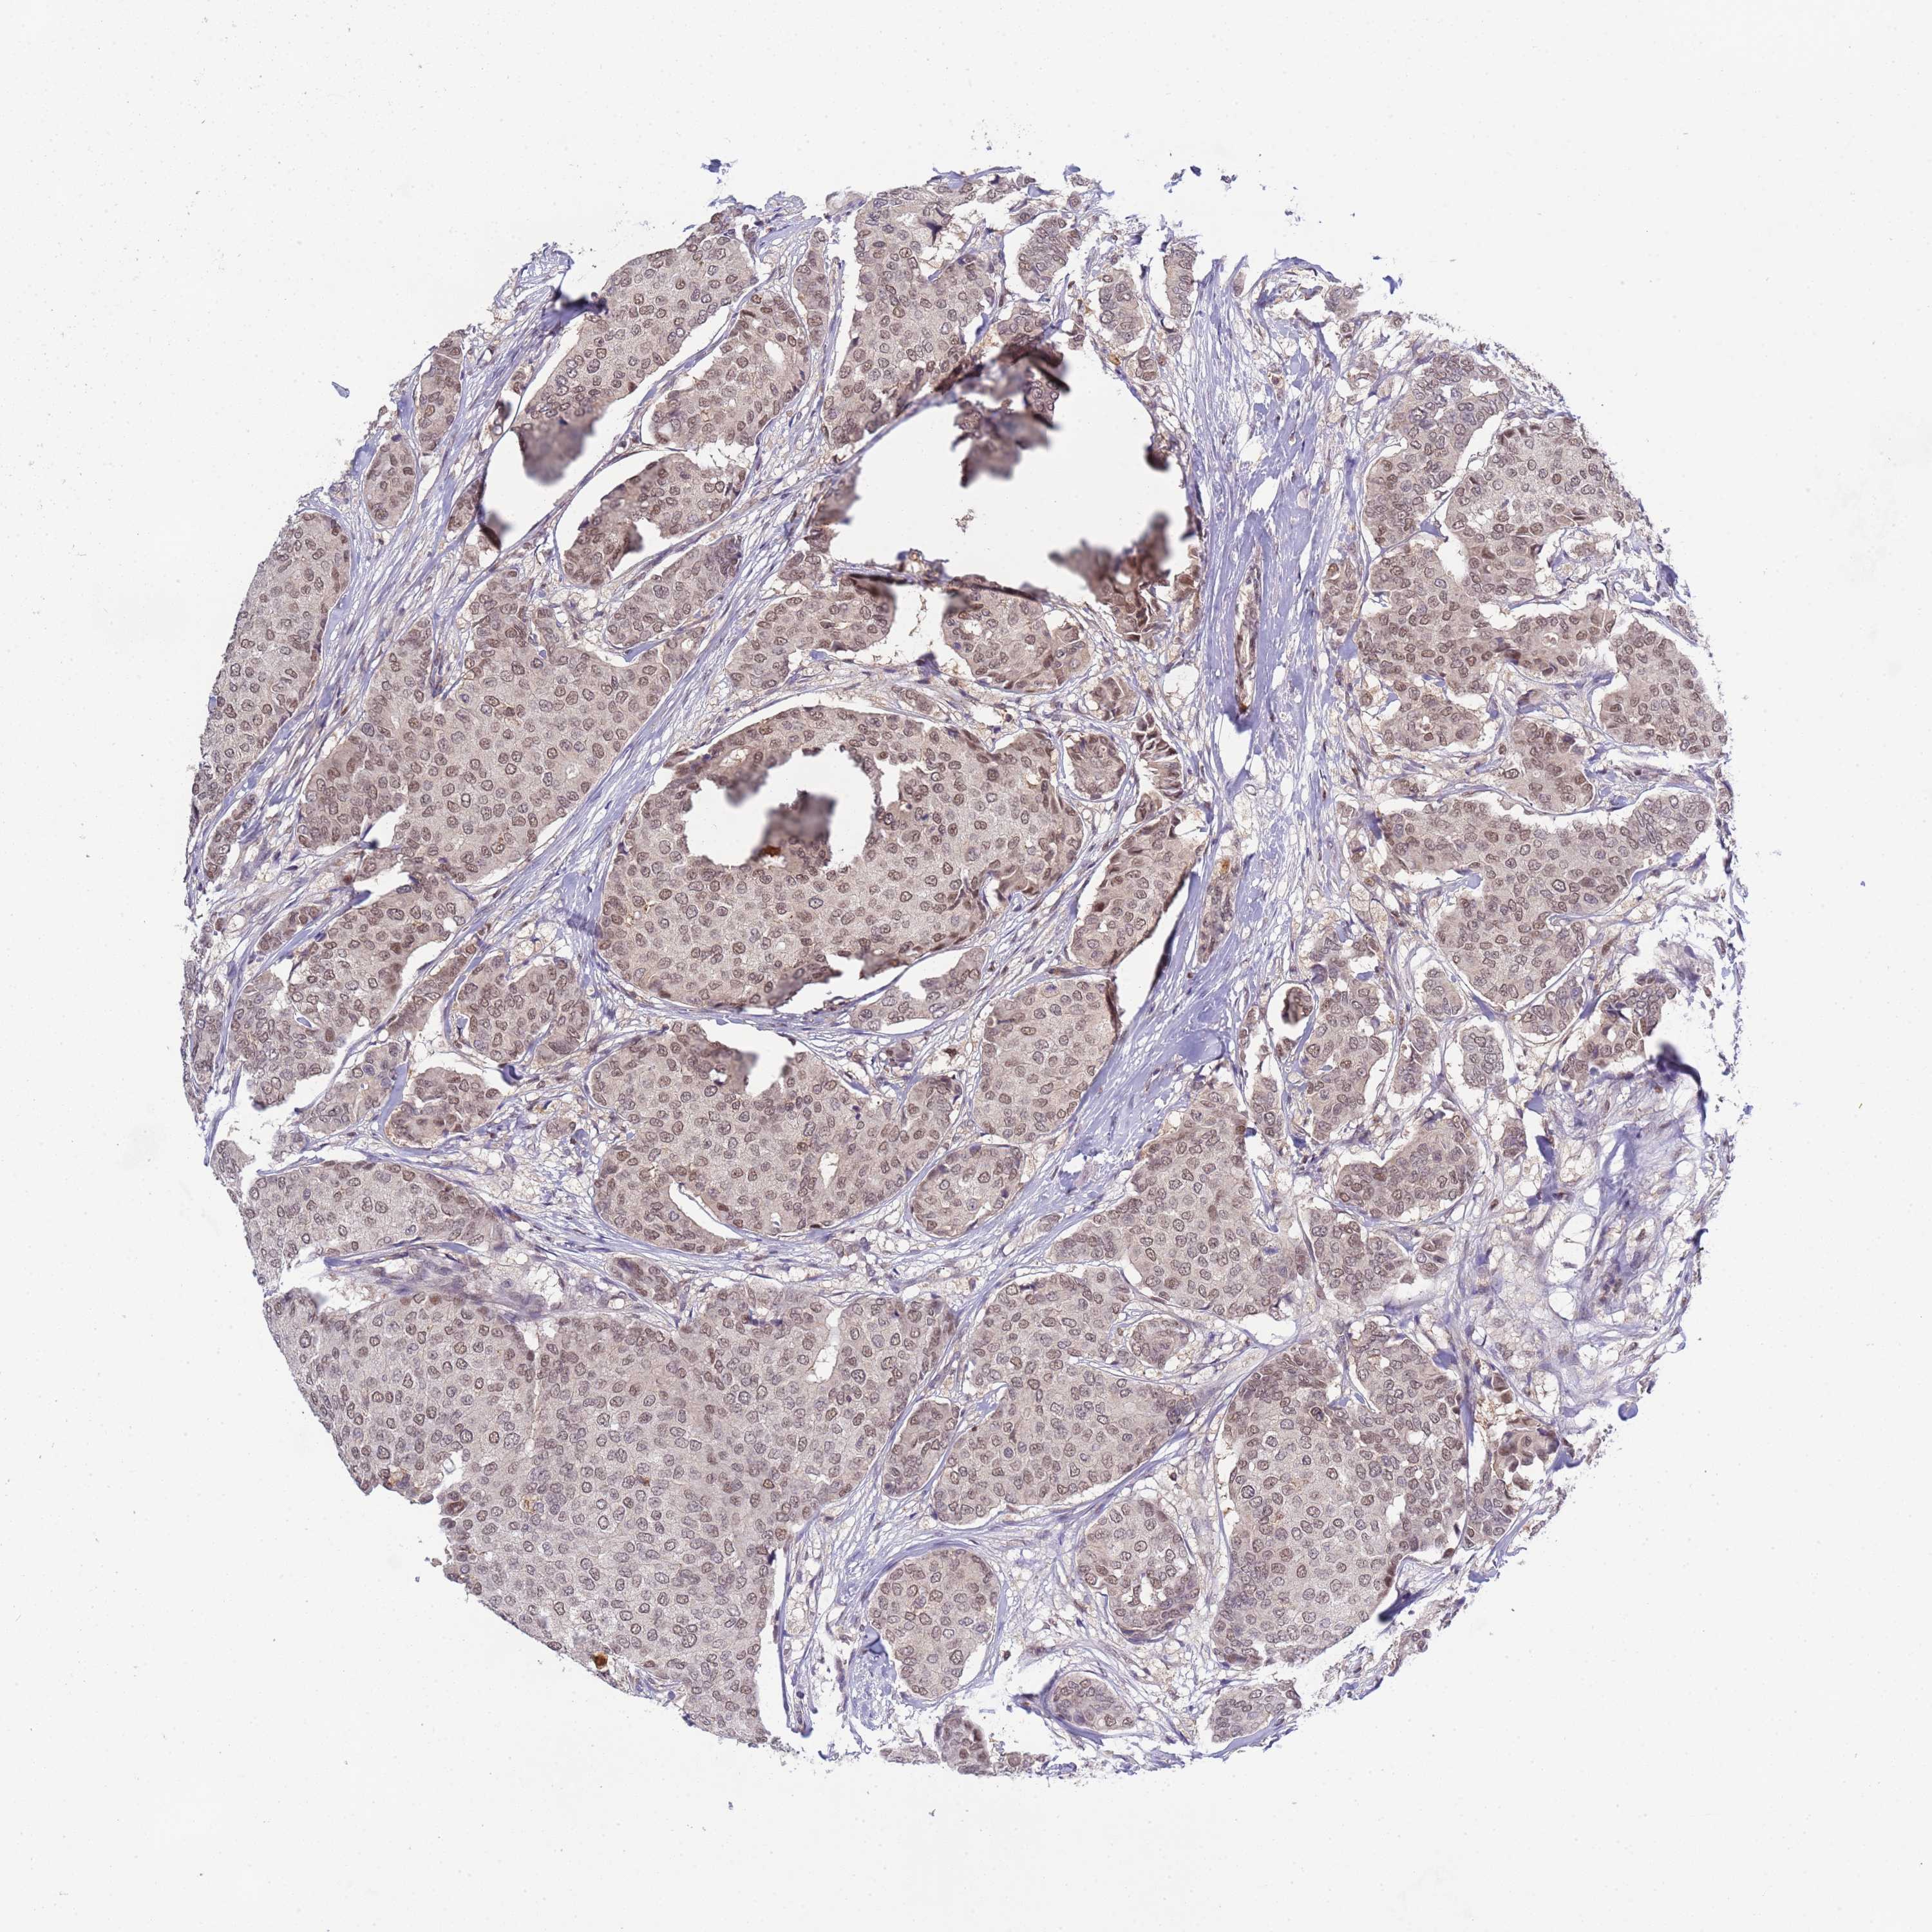

CANCER BREAST CANCER Show tissue menu

BRCA TCGA BRCA VALIDATION PROTEIN EXPRESSION

Breast cancer

Human cancer

CD53 is not prognostic in Breast Invasive Carcinoma (TCGA)